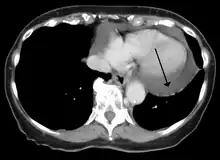

Cardiac CT and MRI scans: cross-sectional imaging with computed tomography (CT) can help localize and quantify the effusion, especially in a loculated effusion (an effusion contained to one area).[12] CT imaging also helps assess for pericardial pathology (pericardial thickening, constrictive pericarditis, malignancy-associated pericarditis).[1] Whereas cardiac MRI is reserved for patients with poor echocardiogram findings and for assessing pericardial inflammation, especially for patients with continued inflammation despite treatment.[5] CT and MRI imaging can also be used for continued follow up on patients.